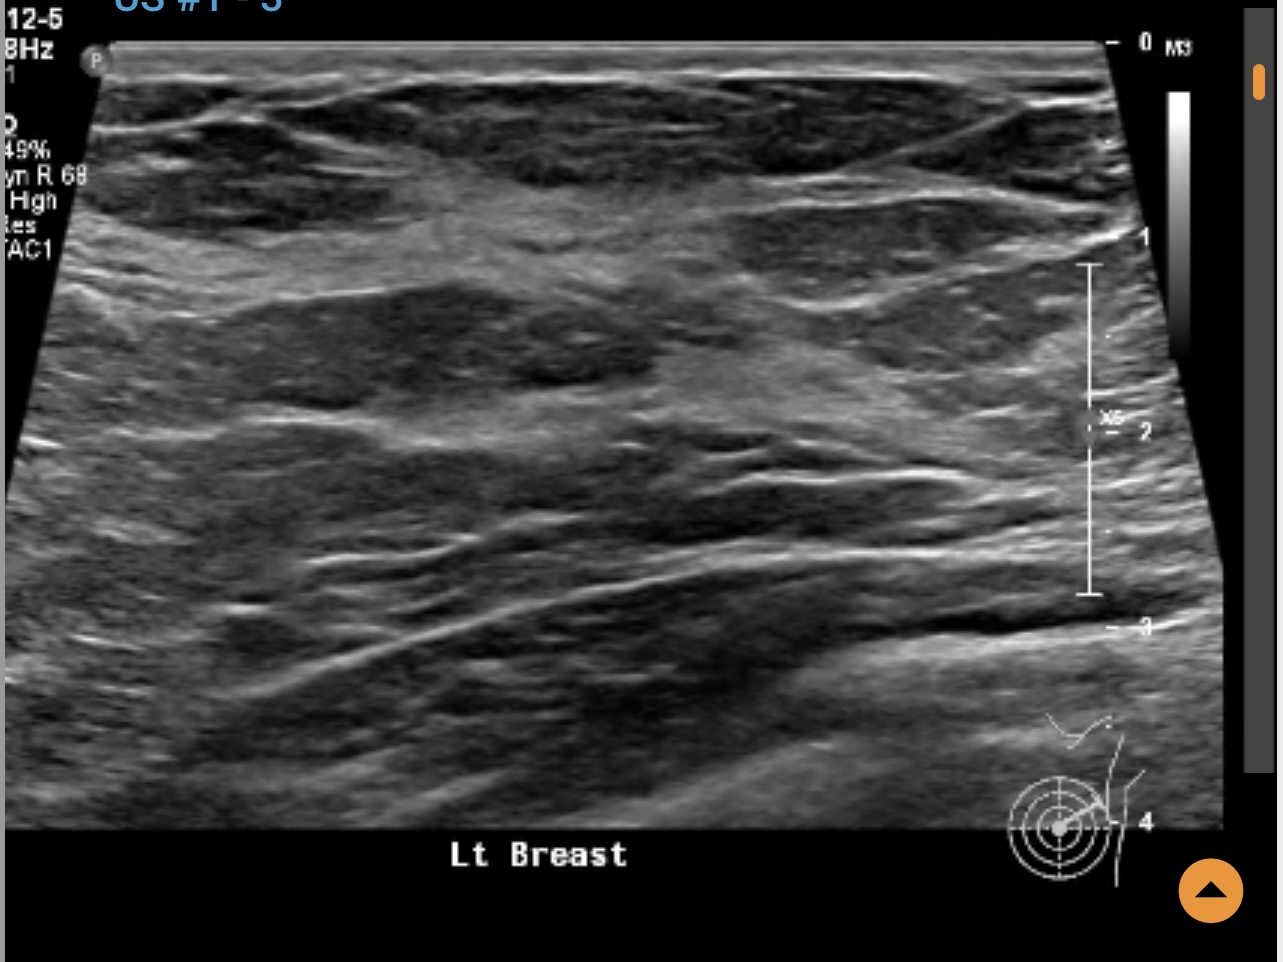

Left breast ultrasound report said no concerns. Symptoms - enlarged lymph nodes left breast, small cyst, changes in size and shape of left breast, dimples in lower left breast, pain in outer quadrant of left breast. Second opinion on ultrasound pics?